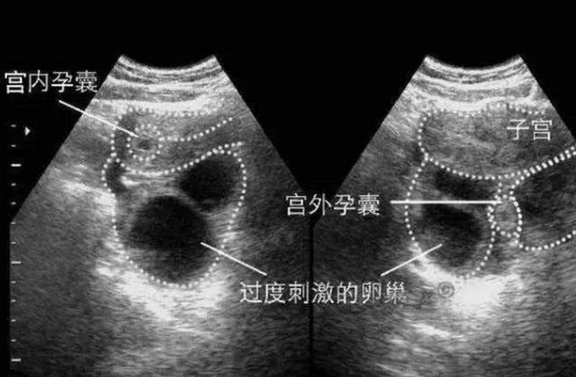

宮外孕打掉最佳時(shí)間,了解宮外孕及其處理時(shí)機(jī)的重要性,宮外孕處理最佳時(shí)間解析,了解宮外孕及其處理的重要性

摘要:了解宮外孕及其處理時(shí)機(jī)的重要性。宮外孕打掉的最佳時(shí)間通常在早期發(fā)現(xiàn)時(shí),一般在妊娠的前三個(gè)月內(nèi)。及時(shí)診斷和治療能夠降低并發(fā)癥的風(fēng)險(xiǎn),保護(hù)女性的健康。對于有性生活的女性來說,了解宮外孕的癥狀和及時(shí)就醫(yī)非常重要,以便...